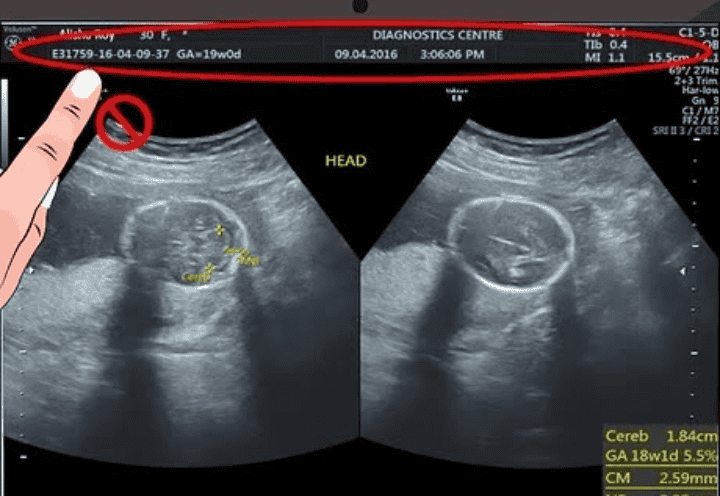

अपनी गर्भावस्था की अल्ट्रासॉउन्ड रिपोर्ट पढ़ने के लिए सबसे पहले हर अल्ट्रासाउंड में EDD (estimated delivery Date ) तथा LMP (लास्ट मेन्स्त्रुअल पीरियड )के बारे में जो भी जानकारी दी जाती है उसका मतलब यह है कि प्रेग्नेंट होने से पहले महिला की लास्ट पीरियड किस डेट में आयी थी और EDD का मतलब होता है डिलीवरी किस तारिख को हो सकती है, दरअसल मे डिलीवरी की तारीख पक्की नहीं होती है। लेकिन फिर भी अंदाजा लगाया जा सकता है कि डिलीवरी इस तारिख के पहले या आगे हो सकती है और लेबर पैन शुरू हो सकता है।